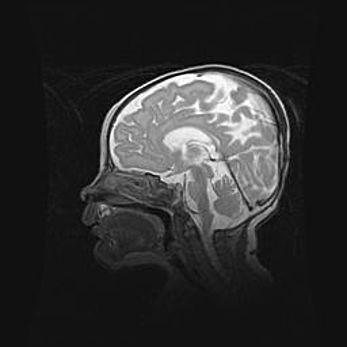

Церебральная ишемия II.

Возраст: 5 дней

Вес: 3400 г

Пол: женский

Окружность головы: 35 см

Срок гестации: 39 недель

Церебральная ишемия – это заболевание, характеризующееся недостаточностью (гипоксией) либо полным прекращением (аноксией) снабжения мозга кислородом по причине закупорки одного или нескольких сосудов. Это приводит к  что метаболическим расстройствам различной степени тяжести в тканях головного мозга, развитию коагуляционных некрозов и гибели нейронов.